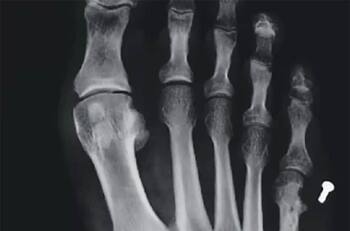

Clínica en Providencia deberá pagar $26 millones a paciente: le dejaron un tornillo dentro del pie